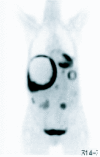

Gastrointestinal stromal tumours (GISTs) comprise a group of smooth muscle mesenchymal alimentary tract tumours of variable malignancy. Recently, the pathophysiology and radiology of these tumours has generated enormous interest following the discovery of a specific, highly effective, chemotherapeutic agent in the form of ST-571 (Imatinib; Glivec, Novartis, Frimley UK). At the time of this review, 106 patients with malignant gastrointestinal stromal tumours seen at the Royal Marsden Hospital have been entered into trials examining the efficacy of varying doses of Imatinib. Burkill et al., also from the Royal Marsden Hospital, have previously reported the distribution, imaging features and pattern of metastatic spread of these tumours (Burkill GJ, Badran M, Al-Muderis O et al. Malignant gastrointestinal stromal tumor: distribution, imaging features, and pattern of metastatic spread. Radiology 2003; 226: 527-32). This new review re-examines the radiological features of GISTs at presentation and well as their changed imaging features following treatment with Imatinib.